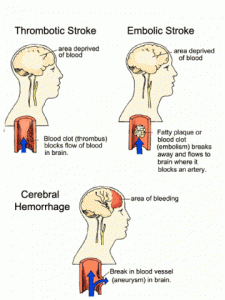

ACCIDENTUL VASCULAR CEREBRAL. NOTIUNI CLINCE

ACCIDENTUL VASCULAR CEREBRAL. NOTIUNI CLINCE Un accident vascular cerebral presupune intreruperea brusca a aportului sanguin intr-o anumita regiune a creierului, ceea ce conduce la o leziune permanenta a creieruluiCiteste tot ... 710 cuvinte

Dimensiune mica

+ cu imagini |